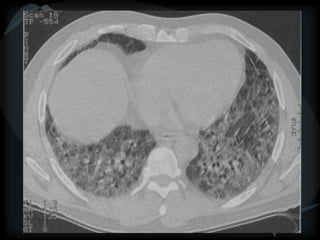

Mosaic CT Patterns

 Ground glass – inflammation/ fibrosis

 airway obstruction (best seen on expiration)

 Vascular obstruction

Airway obstruction

Vascular obstruction